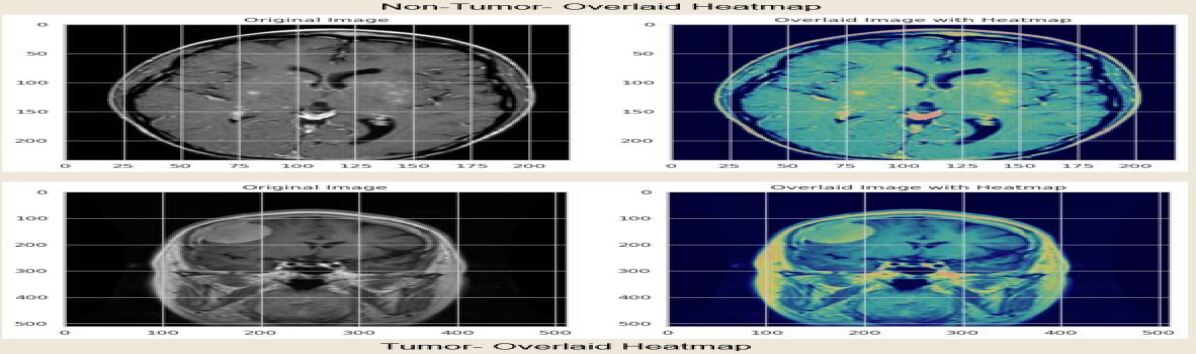

Grad-CAM: Grad-CAM is a method that XAI uses to visually explain decisions made by ensemble models, particularly for applications like brain tumor detection. Grad-CAM highlights regions with the most significant impact on the model’s prediction by superimposing a heatmap on the input image. In the context of brain tumor detection, this method provides invaluable insights by identifying specific regions in MRI images that the model considers indicative of the presence or absence of a tumor, thereby enhancing the transparency and reliability of the model’s decision-making process. This mathematical equation represents the fundamental principle of Grad-CAM:

As shown in Figures 6, 7, and 8, the proposed ensemble model, which employs proficient DL architectures, is coupled with XAI techniques, namely SHAP, LIME, and Grade-Cam, for clear visualization of model decisions. This method simplifies intricate AI decision-making for medical professionals and enhances the system’s credibility. The color-coded visualizations improve interpretability by facilitating rapid comprehension of the factors influencing the model’s predictions. These visualizations precisely depict influential features for a specific prediction, facilitating informed decisions. This technique bridges the gap between complex AI processes and practical healthcare applications, paving the way for the ethical use of AI in healthcare.

Figure 8: Grad-Cam explainable visualization.